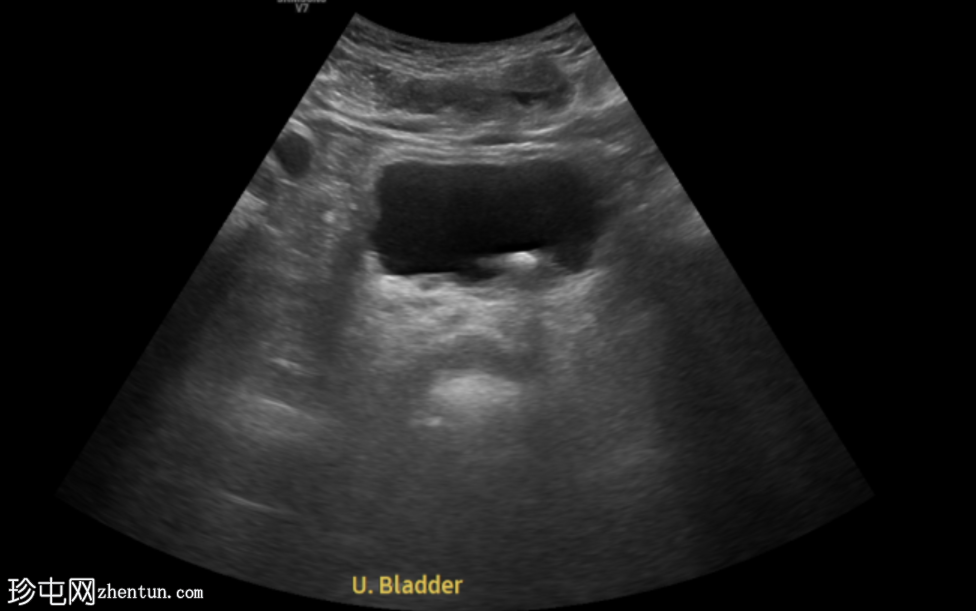

超声

检查

超声显示左侧轻度肾积水,由膀胱输尿管连接处一枚7毫米的远端输尿管结石阻塞所致,输尿管射流正常。